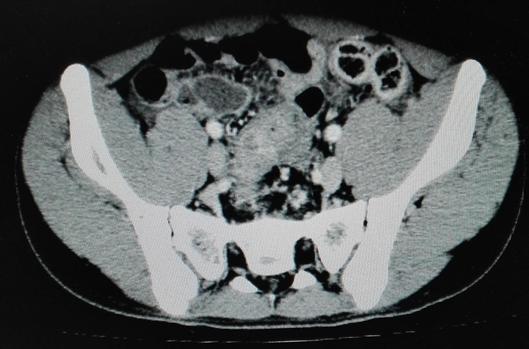

克唑替尼口服3日后,患儿腹部肿块逐渐缩小至4cm*3cm;口服第6天,腹部较前变软,未再排血便,神智较前转清,对答切题。体查:三凹征(-)中下腹部包块3cm*3cm。口服克唑替尼后第12天,患儿无胸水流出,能自行进食,腹部肿块缩小至2cm*2cm,患儿出院。患儿不规律口服克唑替尼一个月后,自行停药。复查腹部CT:腹腔大网膜肿块,互相融合,最大约7.1cm*4.7cm,较初诊外院片缩小。

2017年4月28日CT:腹膜、大网膜增厚、模糊,见多发结节,较大结节约12mm*10mm,增强轻中度均匀强化,结节较前缩小。腹盆腔多发结节,较前缩小。

停口服药治疗后3个月